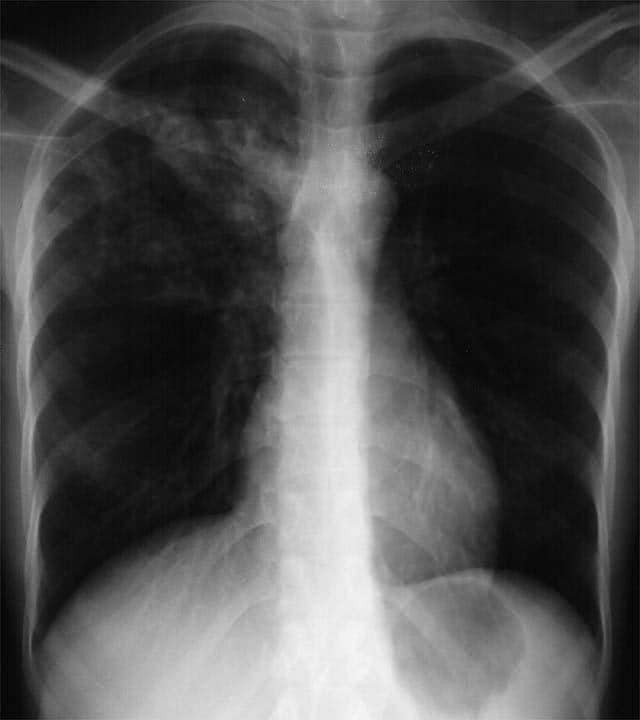

Foto rontgen dada penderita TBC. Foto: medscape.com